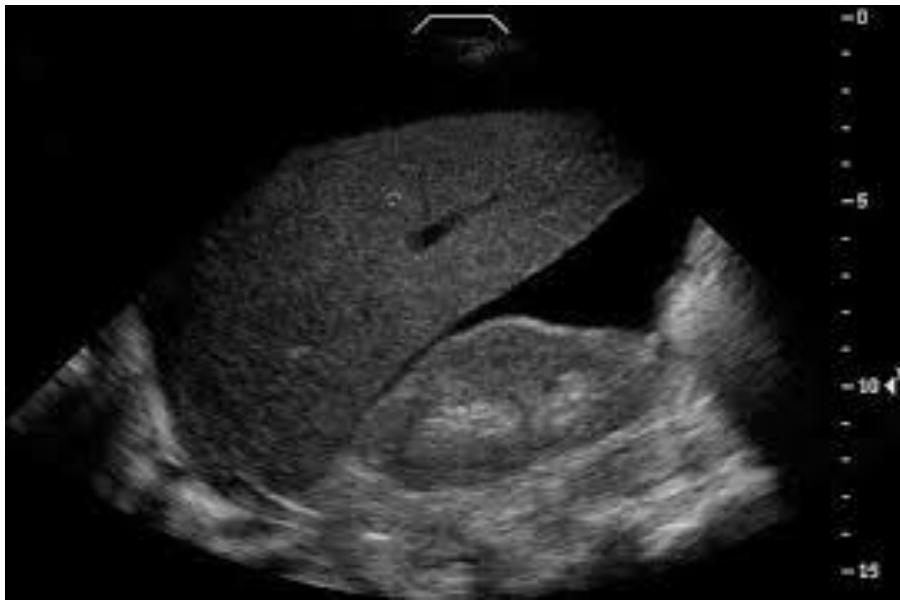

FAST / eFAST Ultrasound

- Modality: Focused Assessment with Sonography in Trauma (FAST).

- Standard 4 Views:

- RUQ (Morisonโs Pouch): Hepatorenal recess.

- LUQ: Splenorenal recess.

- Pelvic (Pouch of Douglas): Suprapubic window.

- Pericardial: Subxiphoid window.

- eFAST: Includes the pleura to check for pneumothorax/hemothorax.

- Positive Finding: Anechoic (black) fluid collection indicating blood in a trauma patient.